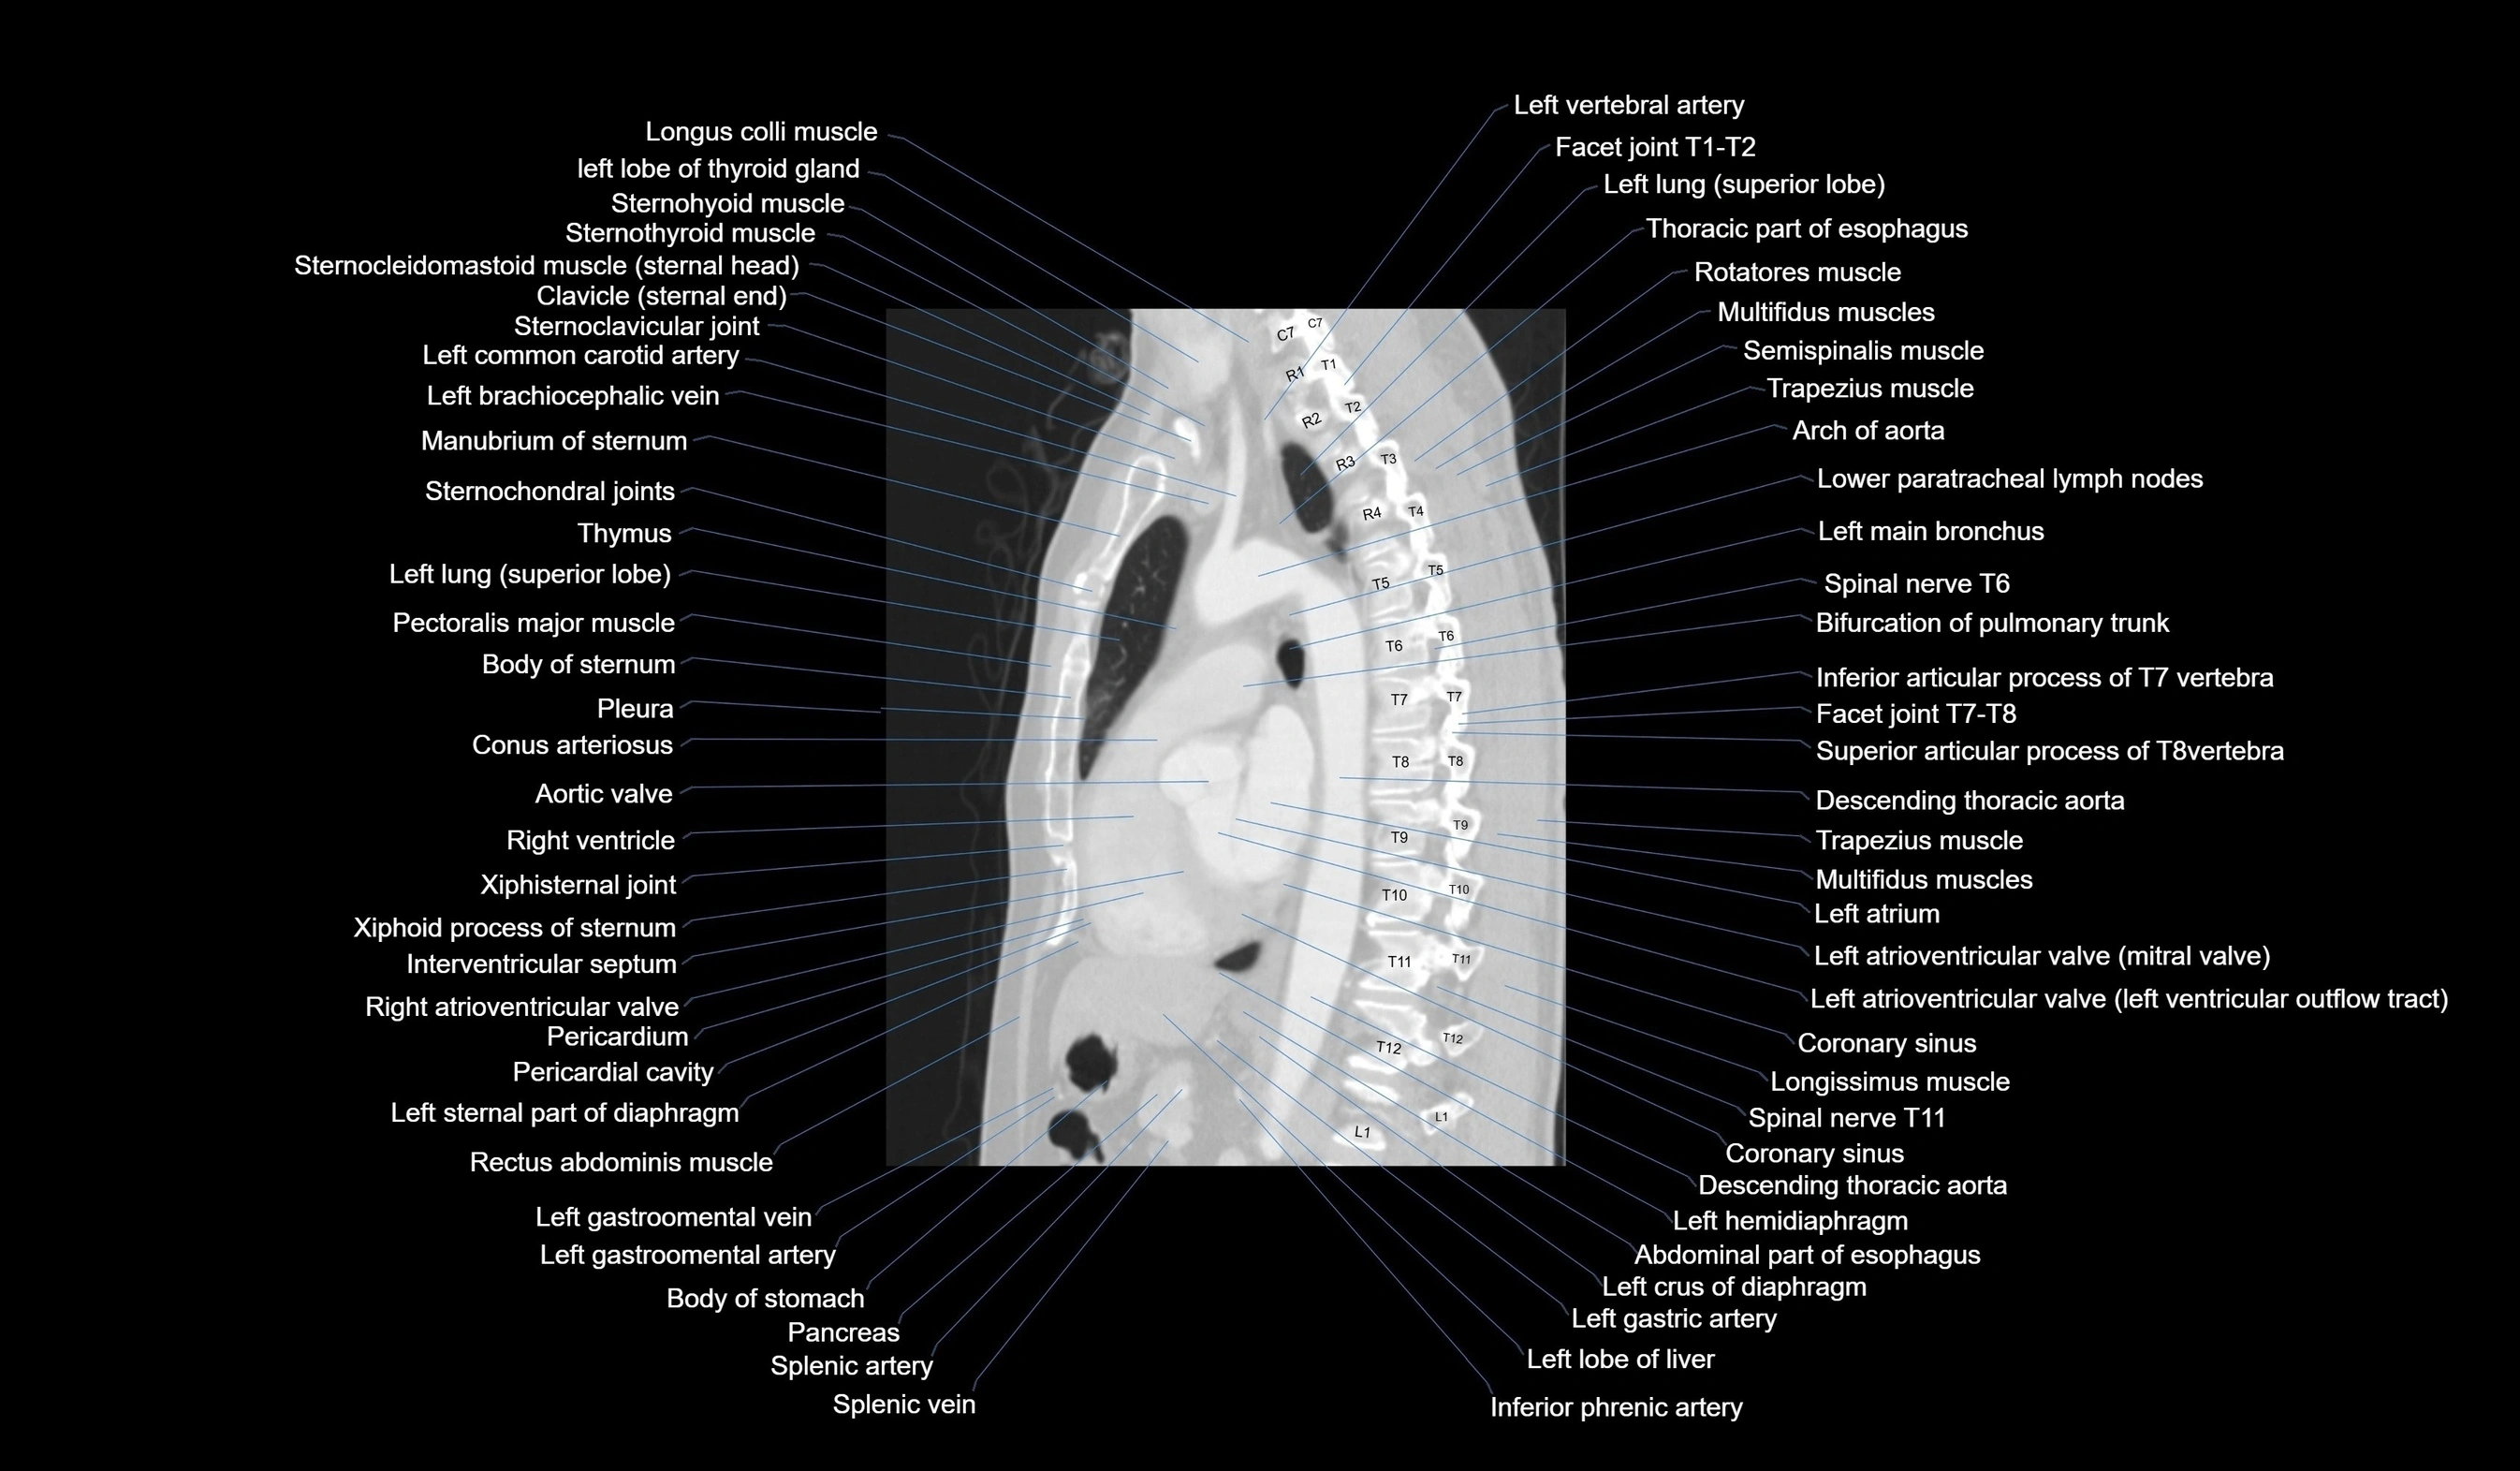

- Longus colli muscle

- Left lobe of thyroid gland

- Sternohyoid muscle

- Sternothyroid muscle

- Sternocleidomastoid muscle

- Clavicle

- Sternoclavicular joint

- Left common carotid artery

- Left brachiocephalic vein

- Manubrium of sternum

- Left Lung (Superior Lobe)

- Pectoralis major muscle

- Body of sternum

- Pleura

- Conus arteriosus

- Aortic valve

- Right ventricle

- Xiphisternal joint

- Xiphoid process of sternum

- Interventricular Septum

- Right atrioventricular valve (tricuspid valve)

- Pericardium

- Pericardial cavity

- Sternal part of diaphragm

- Rectus abdominis muscle

- Left gastro-omental (gastroepiploic) vein

- left gastro-omental artery (left gastroepiploic artery)

- Pancreas

- Splenic artery

- Splenic vein

- Arch of aorta

- Inferior tracheobronchial lymph nodes

- Left main bronchus

- Spinal nerves

- Pulmonary valve

- Left atrium

- Left atrioventricular valve (mitral or bicuspid valve)

- Descending thoracic aorta

- Trapezius muscle

- Multifidus muscles

- Rotatores muscle

- Semispinalis cervicis muscle

- Left hemidiaphragm

- Abdominal part of esophagus

- Right crus of diaphragm

- Left gastric artery

- Left lobe of liver

- Inferior phrenic artery